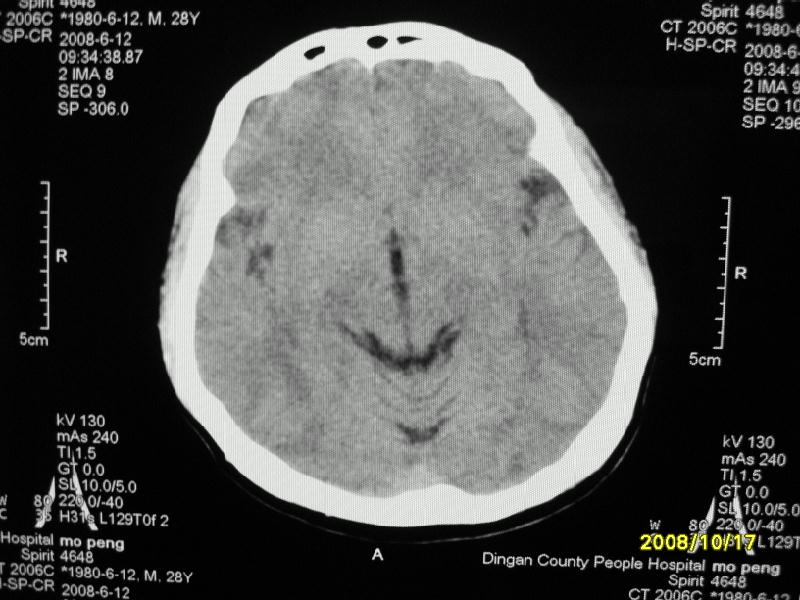

检查名称:     ct颅脑平扫           男     28岁

表现:左顶叶见斑点状致密影。边缘清,大小约0。3*1。0cm,余脑实质密度及灰白质结构示见异常。脑室系统大小,形态,密度未见异常。脑沟。脑裂。脑池未见异常密度影。中线结构无移位。

印象:左顶叶少许钙化灶

左顶叶见斑点状致密影。边缘清,大小约0。3*1。0cm,余脑实质密度及灰白质结构示见异常。脑室系统大小,形态,密度未见异常。脑沟。脑裂。脑池未见异常密度影。中线结构无移位。

印象:左顶叶少许钙化灶。

左顶叶见斑点状致密影